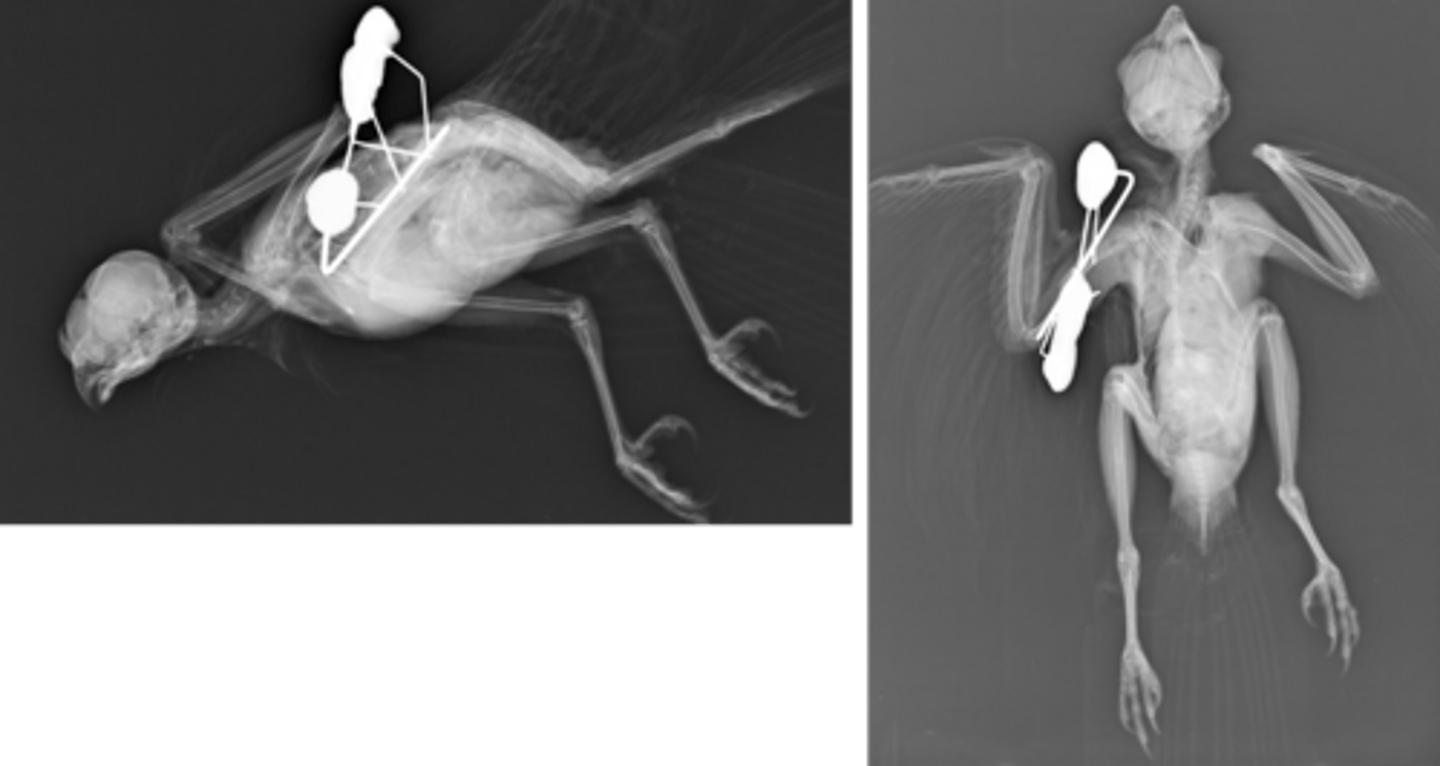

What type of bone structure do avian fractures have?

Pneumatised bone with periosteal blood supply

How do avian bones compare in terms of brittleness?

They are brittle and more splintering

From where do avian bones heal?

Heals from endosteum

What is the healing rate of avian fractures?

Rapid healing

What types of fixation are used for avian fractures?

IM pins and external fixators instead of plates bc thin and brittle bones

avian humeral fracture

-IM pin tied into uniplanar external fixator

-clamps replaced with epoxyresin to reduce weight of device